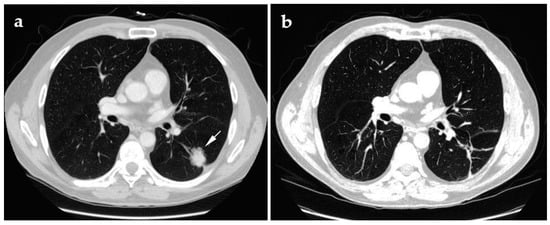

- Chheang, S.; Abtin, F.; Guteirrez, A.; Genshaft, S.; Suh, R. Imaging features following thermal ablation of lung malignancies. Semin. Intervent. Radiol. 2013, 30, 157–168. [Google Scholar] [CrossRef] [PubMed]